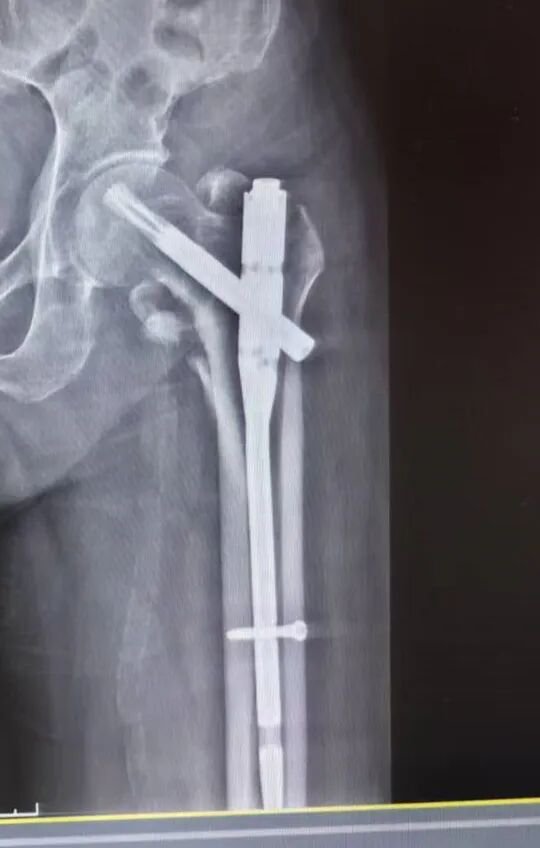

在充分的术前准备后,刘大爷接受了左侧股骨粗隆间骨折闭合复位PFNA内固定术。手术在C型臂X光机精准引导下进行,创伤外二科医疗团队凭借精湛技术,成功完成了微创内固定术,手术过程顺利。